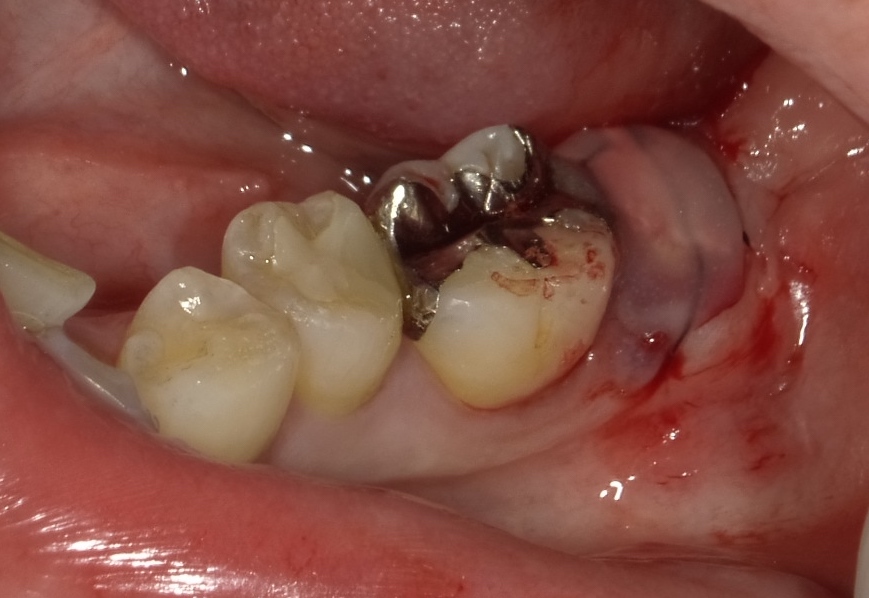

コーヌスデンチャーとは残っている歯に冠のような金属を被せてその上にさらに金属を被せる

2重の冠でできた入れ歯になります。茶筒の原理で固定されるため安定感が高く、審美性や装着感に

優れています。ドイツで開発されたテレスコープデンチャーの一種です。

画像の様なイメージになります。針金を使いませんので

見た目がよくまた維持力も大きくとても良好な義歯となります。